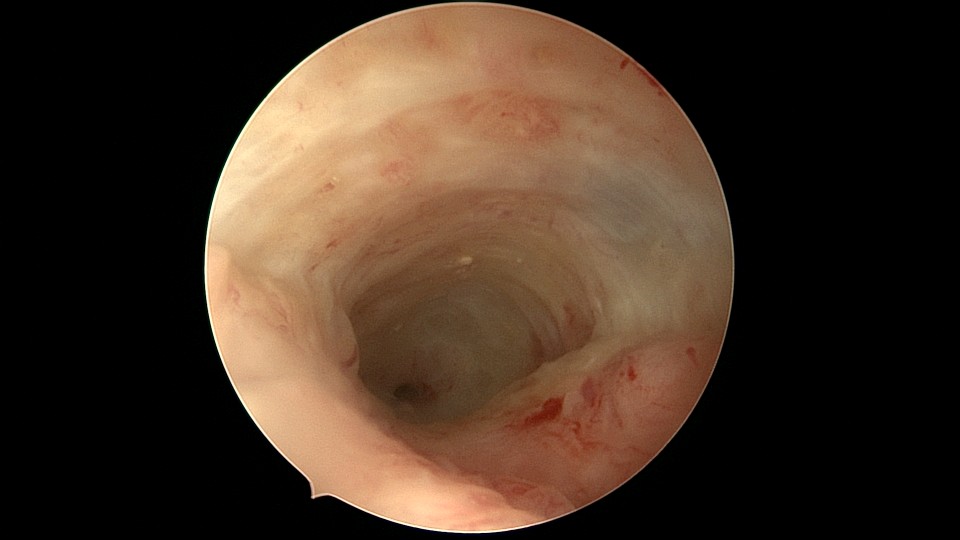

患者54岁,G1P1,剖宫产1次,安环30+年,绝经4年。40年前患者曾行左侧髋关节骨折手术,左下肢外展困难,患者肥胖,阴道很深,金属扩阴器和一次性扩阴器均无法暴露宫颈,用阴道内镜方式进入宫腔,但宫腔镜长度不够,远远能看见环,无法到达环的部位,再次试图暴露宫颈失败,用宫颈钳夹着阴道壁下拉,宫腔镜进入宫腔,但异物钳夹持力度不够,取出失败。用取环钩盲探沿宫腔镜外侧推挤进入宫腔,经历多次拧转,取环钩几乎向前弯成直角,直视下终于钩住节育环,掰直取环钩后缓慢拉出节育环,环变形。